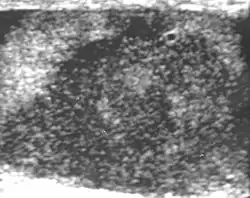

Patients with testicular lymphoma are usually old aged around 60 years of age, present with painless testicular enlargement and less commonly with other systemic symptoms such as weight loss, anorexia, fever and weakness. Bilateral testicle involvements are common and occur in 8.5% to 18% of cases. At sonography, most lymphomas are homogeneous and diffusely replace the testis [Fig. 7]. However focal hypoechoic lesions can occur, hemorrhage and necrosis are rare. At times, the sonographic appearance of lymphoma is indistinguishable from that of the germ cell tumors [Fig. 8], then the patient's age at presentation, symptoms, and medical history, as well as multiplicity and bilaterality of the lesions, are all important factors in making the appropriate diagnosis.

Primary leukemia of the testis is rare. However, due to the presence of blood-testis barrier, chemotherapeutic agents are unable to reach the testis, hence in boys with acute lymphoblastic leukemia, testicular involvement is reported in 5% to 10% of patients, with the majority found during clinical remission. The sonographic appearance of leukemia of the testis can be quite varied, as the tumors may be unilateral or bilateral, diffuse or focal, hypoechoic or hyperechoic. These findings are usually indistinguishable from that of the lymphoma [Fig. 9].

Fig. 9. Leukemia. Diffuse hypoechoic infiltrative lesions are seen involving the whole testis, indistinguishable from that of the lymphoma.